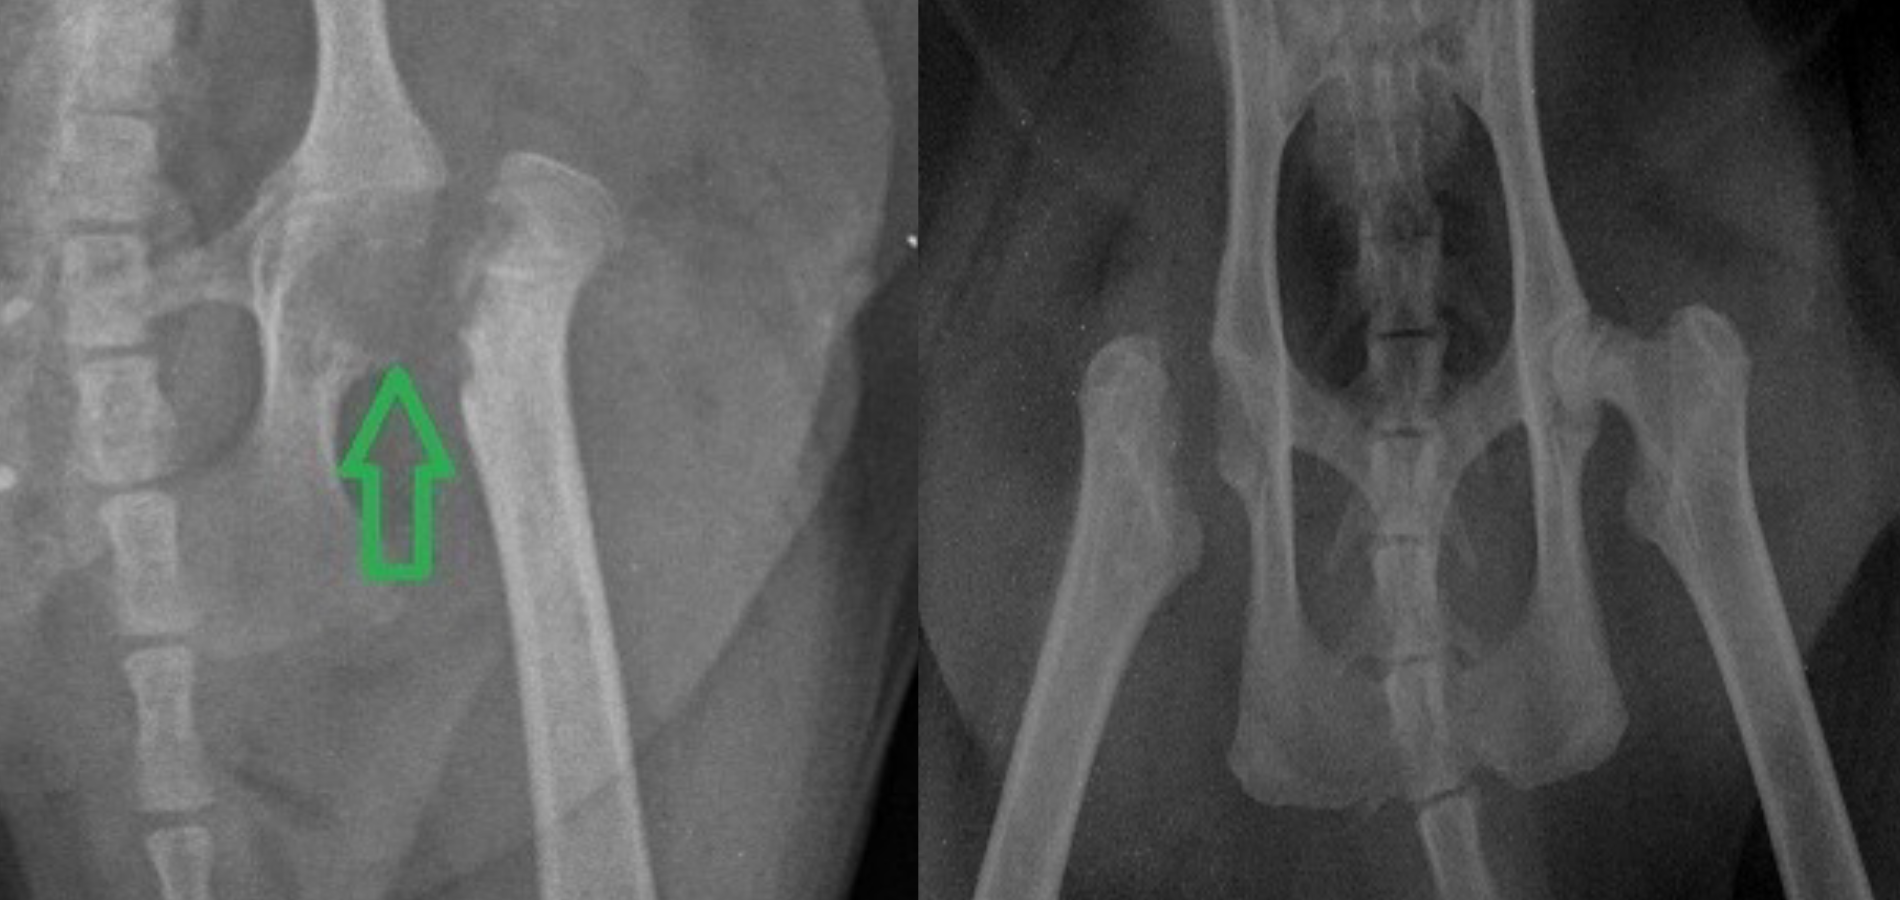

- Резекционная артропластика – удаление поврежденной головки бедра.

(из практики Максима Александровича Кардаша)

После хирургического лечения большинство животных полностью восстанавливаются и ведут нормальный образ жизни. Консервативное лечение помогает только при раннем выявлении болезни. Болезнь Пертеса – серьезное заболевание, но при своевременной диагностике и правильном лечении животное может жить полноценной жизнью!